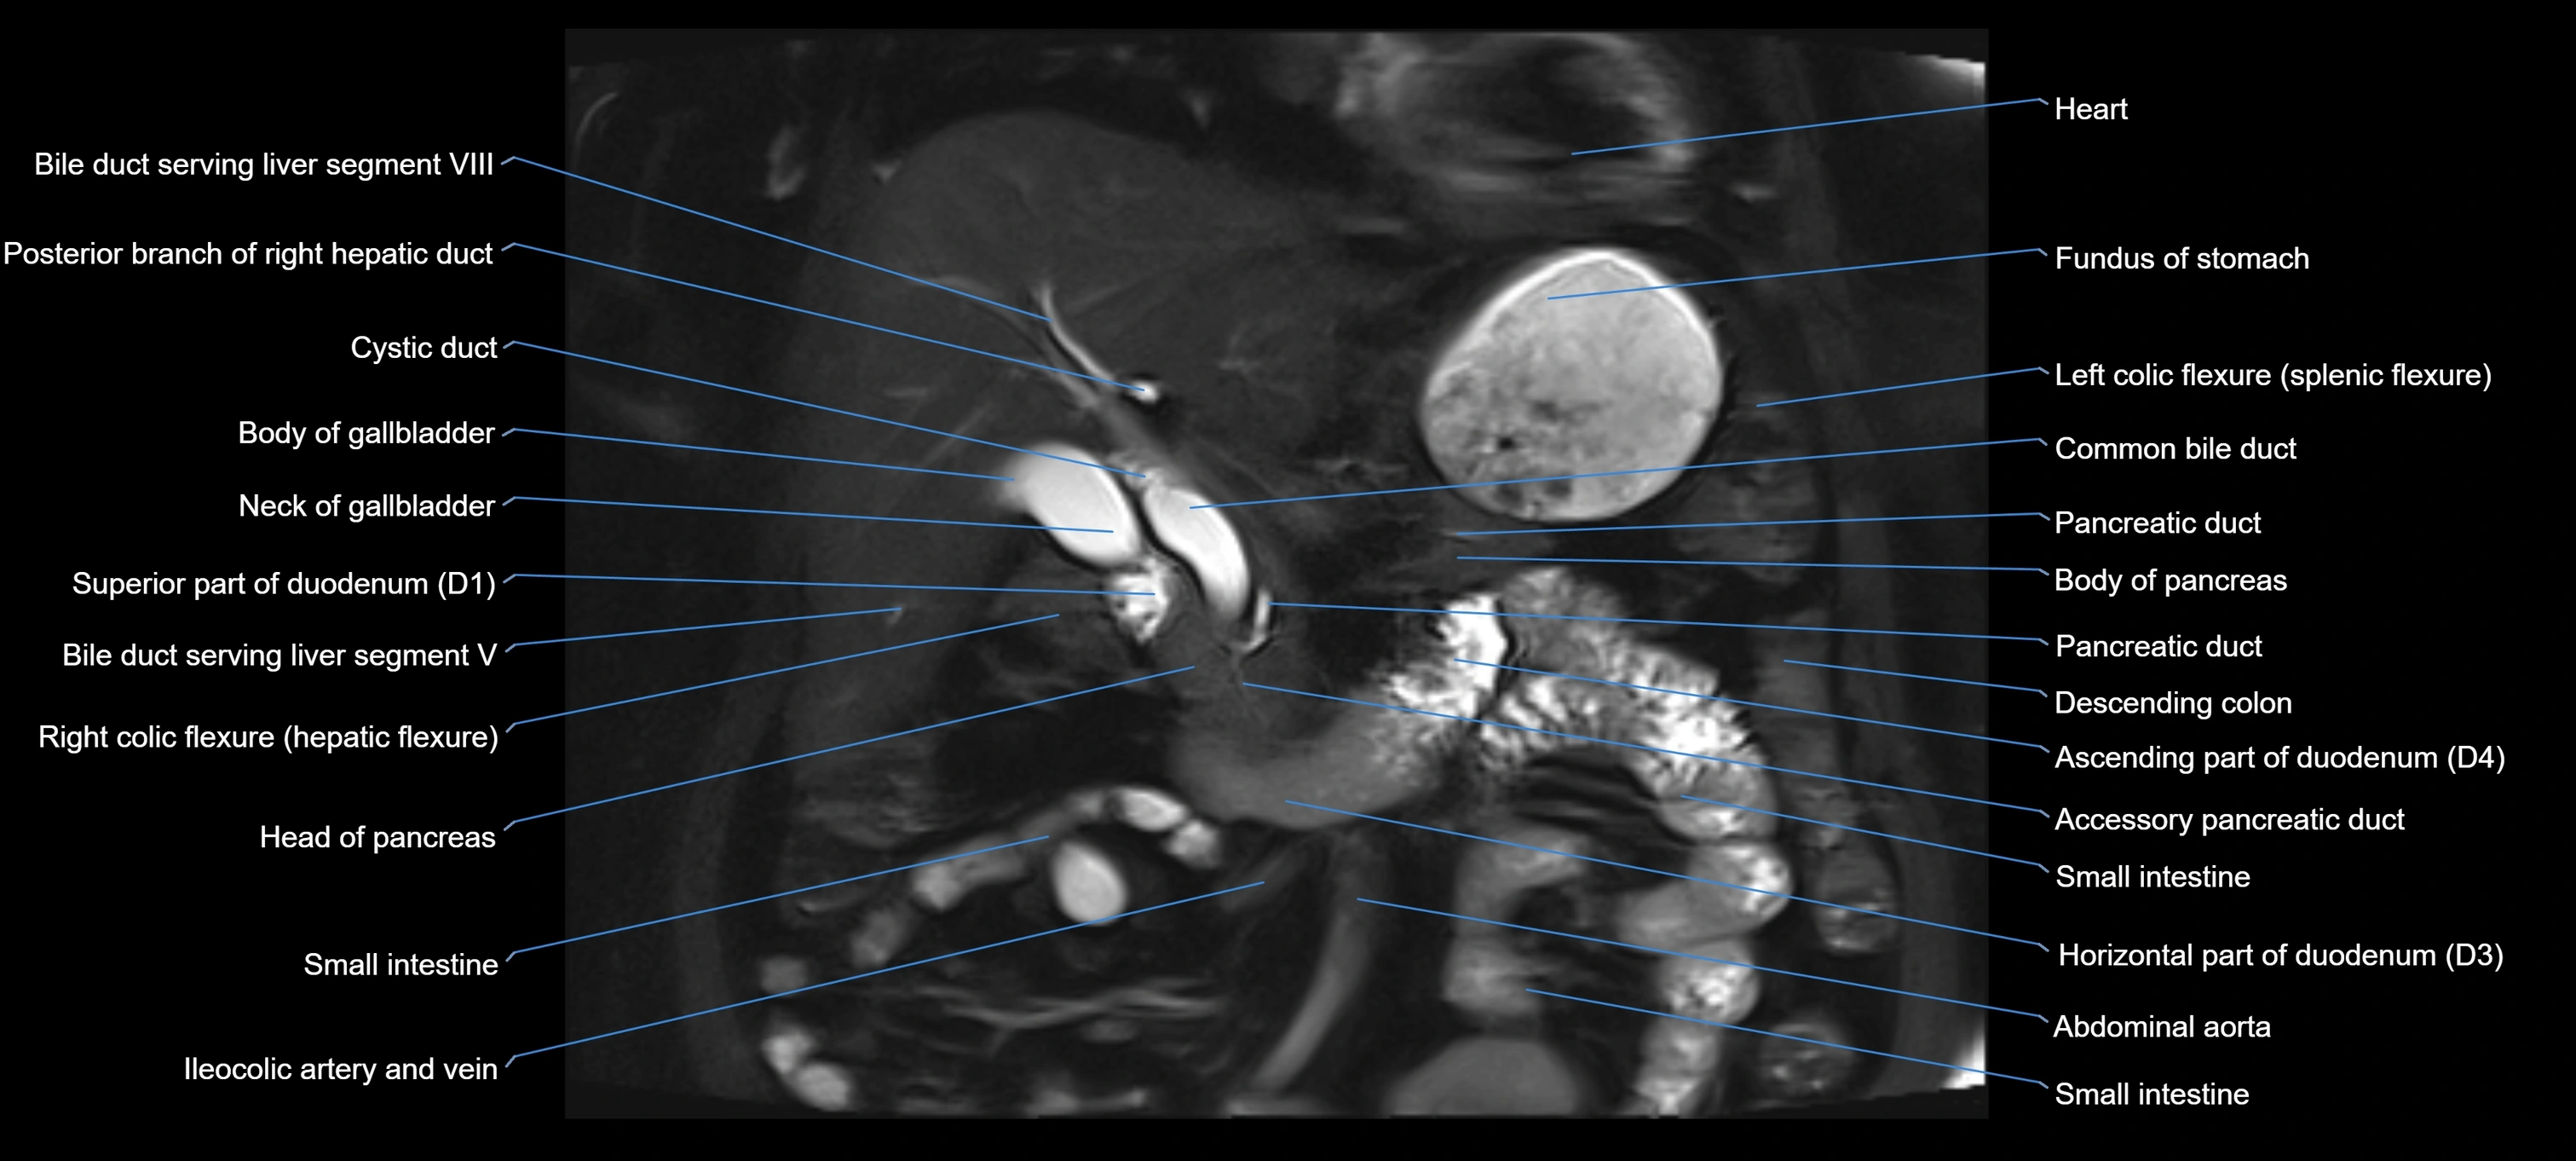

T2 TSE Fat-Saturated 3D (MRCP sequence):

• Duct visualized as a continuous bright tubular structure joining or parallel to the main pancreatic duct

• Allows 3D reconstruction of ductal anatomy and variants

• Excellent for diagnosis of pancreas divisum

Thick-slab T2 Fat-Saturated HASTE:

• Shows the accessory duct as part of the biliary–pancreatic system in a projectional image

• Highlights communication with main pancreatic duct and opening into the minor papilla

• Filling defects (stones, strictures) seen as dark spots within bright fluid

MRI image

image